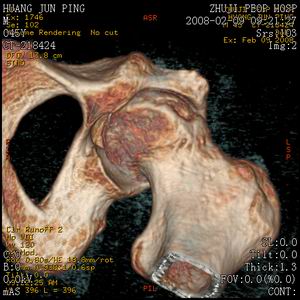

标题: CT11650:左髋病变,请会诊.

左髋疼痛不适近半年,局部无红肿热.无明确外伤病史.黄酒每天二餐.

考虑左侧股骨头缺血性坏死.(常期饮酒引起代谢障碍?)

左侧股骨头缺血性坏死;很典型。

左侧股骨头缺血性坏死,支持!图像有些乱。

“局部无红肿热.无明确外伤病史.黄酒每天二餐”。考虑左侧股骨头缺血性坏死。